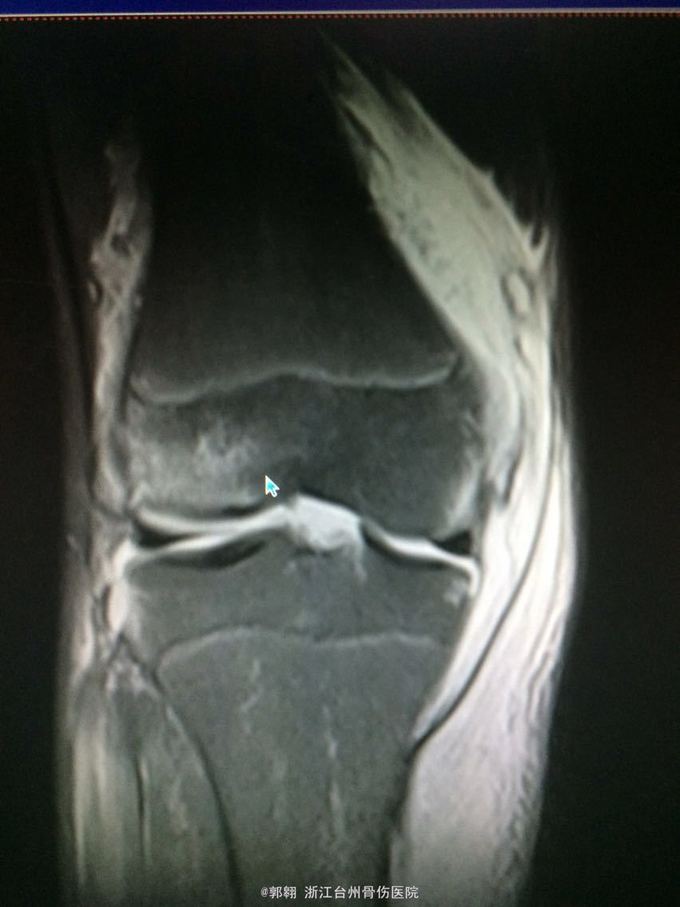

右膝关节跑步摔伤疼痛功能障碍3小时 病史:患者15岁 上体育课时跑步摔倒致右膝关节畸形疼痛 功能障碍,由老师送至医院就诊。

查体:右膝关节及小腿上段肿胀明显,张力较大,压痛位于内侧副韧带股骨处和膝关节外侧,膝关节波动感,浮髌试验阳性、扳膝试验阳性、抽屉试验阳性、Lachman阳性、膝关节屈伸活动因疼痛而障碍,足背动脉波动良好。 MRI:右膝关节股骨内髁骨折 胫骨平台外侧缘骨折

诊断:右膝关节内侧副韧带撕裂 前交叉韧带损伤 股骨内侧髁骨折胫骨平台外侧缘骨折 腓肠肌肌肉拉伤 处理:制动 支具托固定 冰敷 退肿止血药物治疗